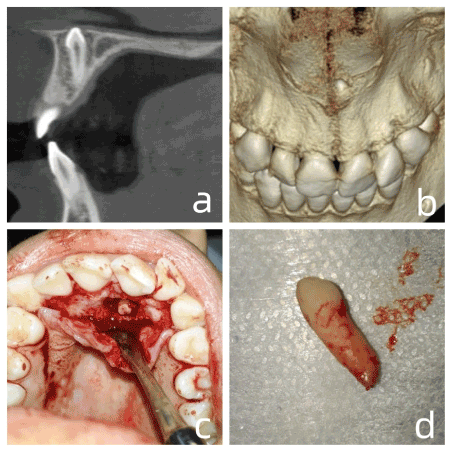

A female patient, melanoderm, 16 years old, and presenting no systemic changes was referred for extraction of an included tooth. Through panoramic radiography, an inverted mesiodens was observed between tooth 11 and 21. Being impossible to determine the vestibulo-palatal position of the referred tooth, a CBCT was requested for better evaluation. Evaluating the CBCT in detail, the inverted mesiodens and palate location were confirmed Figure 2a, and in the 3d reconstruction (Figure 2b) we noticed intimate contact with the nasal fossa. Anesthesia was performed both in the bottom of the buccal groove of tooth 21, and in the incisor foramen. An envelope incision was performed (#15 blade) involving the gingival sulcus from tooth 23 to tooth 13, followed by high-speed osteotomy with a #6 spherical drill to expose the root. The use of elevators to avoid wedge movement, rupture of the nasal membrane, and deviation of the tooth towards the nasal cavity is noted. After the osteotomy (Figure 2c), the root of the tooth was revealed, where #150 forceps were used to manage removal without odontosection (Figure 2d). Finalizing, osteoplasty and abundant washing with saline were then performed, followed by transpapillary suture in the entire anterior region.

Figure 2. a. Sagittal cut showing the position of the supernumerary tooth. b. 3D reconstruction showing proximity to the nasal cavity. c. root portion of the supernumerary exposed after odontosection. d. intact mesiodens

Case 2 presented a tooth located entirely in the palate, in addition to being inverted. Evaluating only a panoramic exam, we might make the mistake of beginning access at the vestibular. However, using tomography the impossibility of carrying such access out is evident, since access by the vestibular, would require very extensive osteotomy. Thus, the CBCT made it possible to plan the extraction with the use of forceps securing the root portion of the supernumerary, and not the crown as is done conventionally.

Contrary to case 1, in case 2 we noticed that the supernumerary crown was in close contact with the nasal fossa, and in case 4 the root of the included canine was also in close contact with the nasal fossa. This information allowed surgical planning to minimize any intrusion, and avoid wedging effect from any instrument, which would make buco-nasal communication more likely. In addition, a fibrin sponge was included at the operating table to resolve any surgical accident involving bucal-nasal communication.